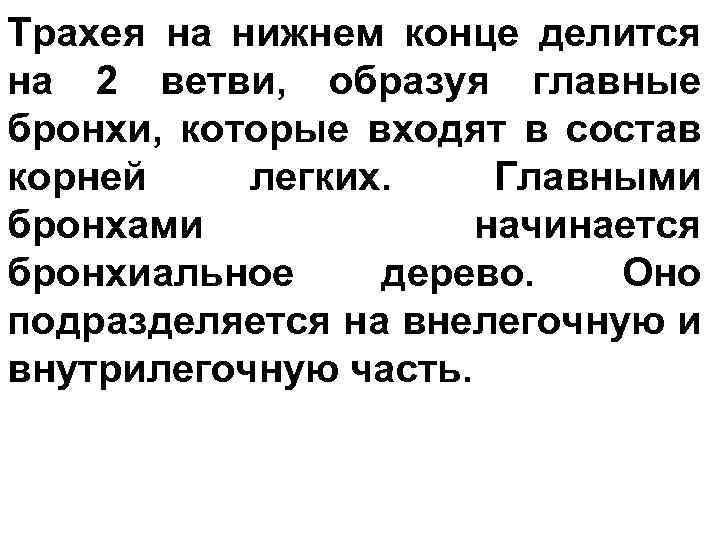

Трахея на нижнем конце делится на 2 ветви, образуя главные бронхи, которые входят в состав корней легких. Главными бронхами начинается бронхиальное дерево. Оно подразделяется на внелегочную и внутрилегочную часть.

Бронхиальное дерево: → долевые → внелегочные зональные бронхи → 10 правый и левый главные бронхи внутрилегочных сегментарных бронхов (бронхи крупного калибра) → субсегментарные бронхиолы (бронхи среднего калибра) → внутридольковые калибра) → междольковые бронхи (бронхи → терминальные бронхиолы малого